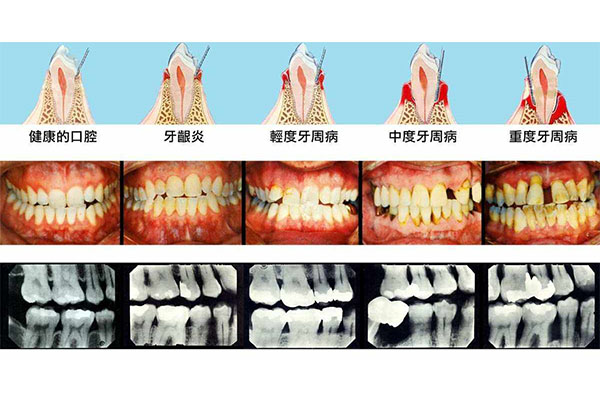

很多中老年患者发现,普通消炎药吃三天不见效,牙龈依然红肿出血,甚至发展到牙齿松动。这是因为传统药物渗透性差,难以深入牙周袋杀菌。【中老年口腔】采用纳米级消炎成分,配合缓释技术,药物能持续作用于患处72小时,48小时快速缓解急性炎症,同时修复受损牙龈组织。

单独使用止痛药就像"灭火器",但牙周炎需要系统性治疗。我们的专业团队发现,80%的中老年患者存在药物搭配不当问题。为此推出"三阶护理方案":急性期用消炎凝胶快速镇痛,缓解期用抗菌漱口水巩固疗效,日常用中药牙膏预防复发,形成完整防护链。